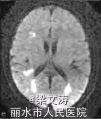

体温38.1℃,意识清楚,定向力、记忆力、计算力等高级皮质功能明显受损;脑神经阴性;四肢肌力V级,肌张力正常,腱反射(++),两侧对称;双侧巴氏征阴性,脑膜刺激征阴性。共济运动及感觉系统查体不能配合。全身浅表淋巴结未触及肿大,两肺未闻及干湿性I罗音,心律齐,腹平软,肝脾肋下未触及,双下肢无水肿。血常规示三系减低[白细胞计数3.6 X109/L(参考范围:4.0 X 109/L一10.0×109/L),红细胞计数2.15×1012/L(参考范围:4.00×10“/L一5.50×1012/L),血小板计数68×109/L(参考范围:100×109/L一300×109/L)],低蛋白血症[清蛋白28.5 g/L(参考范围:35.o一52.0g/L)];红细胞沉降率、肝肾功能及电解质均正常,维生素 B。:、叶酸正常,3次血培养均阴性;艾滋病抗体阴性;抗核抗体、肿瘤标志物、自身抗体及抗中性粒细胞胞质抗体(ANCA)阴性,免疫球蛋白M轻度降低[0.28 g/L(参考范围:0.46—3.04 g/L)];乳酸脱氢酶[1 120 U/L(参考范围:135—225 U/L)]和血13:微球蛋白[3.7 mg/L(参考范围:1.0—2.5 zng/L)]明显增高。腰椎穿刺脑脊液检查示:压力150 illln H20(参考范围:80—180柚H20,1 mm H20=0.0098 kPa),白细胞计数7×106/L[参考范围:(0—10)X100/L],蛋白2.80 g/L(参考范围:o.10—0.25 g/L),cl一107 rnmol/L(参考范围:120—130 n吡nol/L),糖3.5 mol/L(参考范围:2.5~4.5 mmol/L);细胞学正常;IgG指数0.099;JCV—DNA阳性;单疱病毒、柯萨奇病毒、埃可病毒、巨细胞病毒等抗体阴性;墨汁染色阴性,细菌加真菌培养阴性。2010—0l一19流式细胞术检查示co;/cD毒(85%)轻度增高,co;co;、coco;、cD五cD未基本正常,CDI;(2%)明显减低。2.3影像学检查2009—12—25腹部CT提示脾脏偏大, 2010-01—12复查腹部CT提示脾脏肿大、两侧肾上腺区团块影。2009—12—29颅脑MtlI示两侧半卵圆中心、侧脑室旁多发病变009—12—24骨髓穿刺检查示有核细胞增生活跃,红系/粒系(G/E)=0.87:1;中性粒细胞增生(占40.4%),以中性中间阶段粒细胞为主;红细胞增生(占 46.4%),以中晚幼红细胞为主;淋巴细胞比例下降;血小板计数较少,吞噬细胞增多,未见明显异常细胞

患者2009—12—27入住感染科,予头孢哌酮针及阿奇霉素针抗感染等治疗,病情无明显好转。2009—12—29行颅脑MPd检查示脑内多发脱髓鞘样病灶,于2010—01—06转入神经内科并行相关检查。根据该患者的临床和影像学特征,结合脑脊液中JCV的DNA序列检测以及骨髓穿刺病理活检结果,诊断为弥漫大B细胞淋巴瘤并发PML可能。虽经退热、补液,纠正贫血、低蛋白血症等积极治疗,但患者病情仍迅速进展,于2010—01—28凌晨出现呼吸、心搏停止,予气管插管、心肺复苏等积极抢救治疗后呼吸、心搏恢复。患者自动出院1 d后死亡,家属拒绝尸检

本例患者表现为视觉障碍、认知功能减退和精神行为异常等典型的PML症状,颅脑MRI检查符合典型的PML影像学表现;脑脊液中检测到JCV的DNA序列,病理活检证实弥漫大B细胞淋巴瘤侵犯骨髓,并且缺少其他感染或肿瘤的依据。因此,本例患者诊断为弥漫大B细胞淋巴瘤并发PML。PML患者通常处于免疫抑制状态,在此基础上需要与其他颅内多发病灶鉴别,如中枢神经系统血管炎、原发性中枢神经系统淋巴瘤以及脑弓形体病等。本例患者病史和实验室检查以及颅脑MRI表现均不支持以上疾病的诊断。目前,针对PML尚无特异的治疗措施,PML患者的预后极差,临床需引起足够的重视。当存在免疫缺陷或免疫抑制的患者出现典型的视觉障碍、认知功能改变、肌无力等症状时,应考虑本病的可能。本例患者虽经积极对症治疗,但患者病情仍迅速进展、恶化。因此,在病程早期行颅脑MRI检查以及腰椎穿刺脑脊液检测JCV的DNA序列,均有助于本病的诊断,必要时可行脑组织活检。明确诊断后应立即开始免疫重建治疗,抑制脱髓鞘的继续进展;同时避免医源性PML也非常重要。